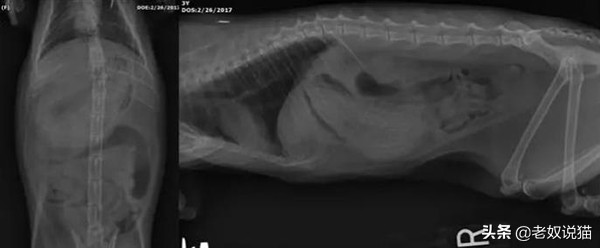

一只5个月大的小猫误食了儿童玩具